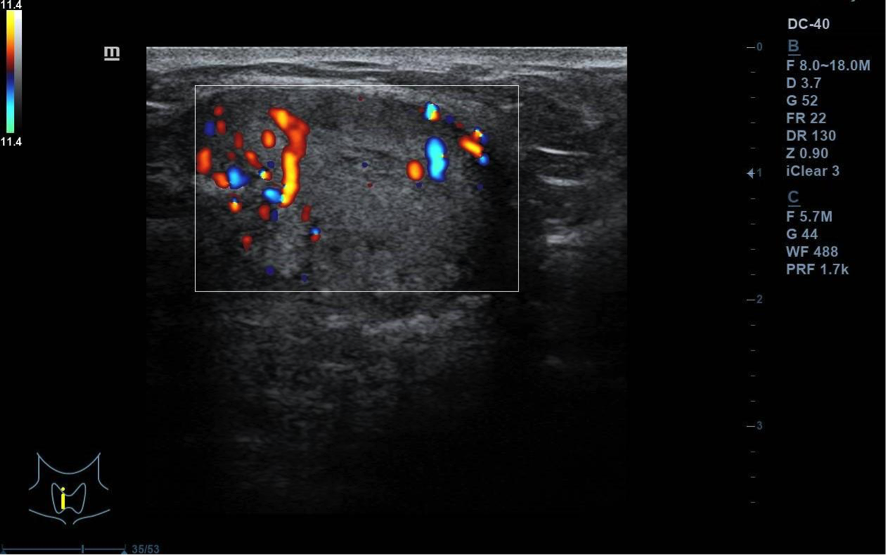

Se visualiza nódulo tiroideo en la unión del istmo con lóbulo tiroideo derecho, sólido, con cierta heterogenicidad, halo grueso anecogénico. Una zona del borde irregular, con mayor señal Doppler y de crecimiento excéntrico. Mide de diámetro máximo 25 x 20 mm. Adenopatías no patológicas.

La paciente fue remitida a Endocrinología para valoración de nódulo tiroideo de 2,5 cm, se solicitó ecografía para PAAF que objetivó nódulo TIRADS-4, PAAF con categoría Bethesda IV: neoplasia folicular con signos de células de Hürtle. Técnica IHQ de Calcitonina negativa. Se envía a Cirugía general y Digestivo para programar cirugía. Se realiza istmectomía y la AP revela que se trata de un tumor folicular de potencial maligno incierto, márgenes libres. Estudio genético con mutación del gen TERT.